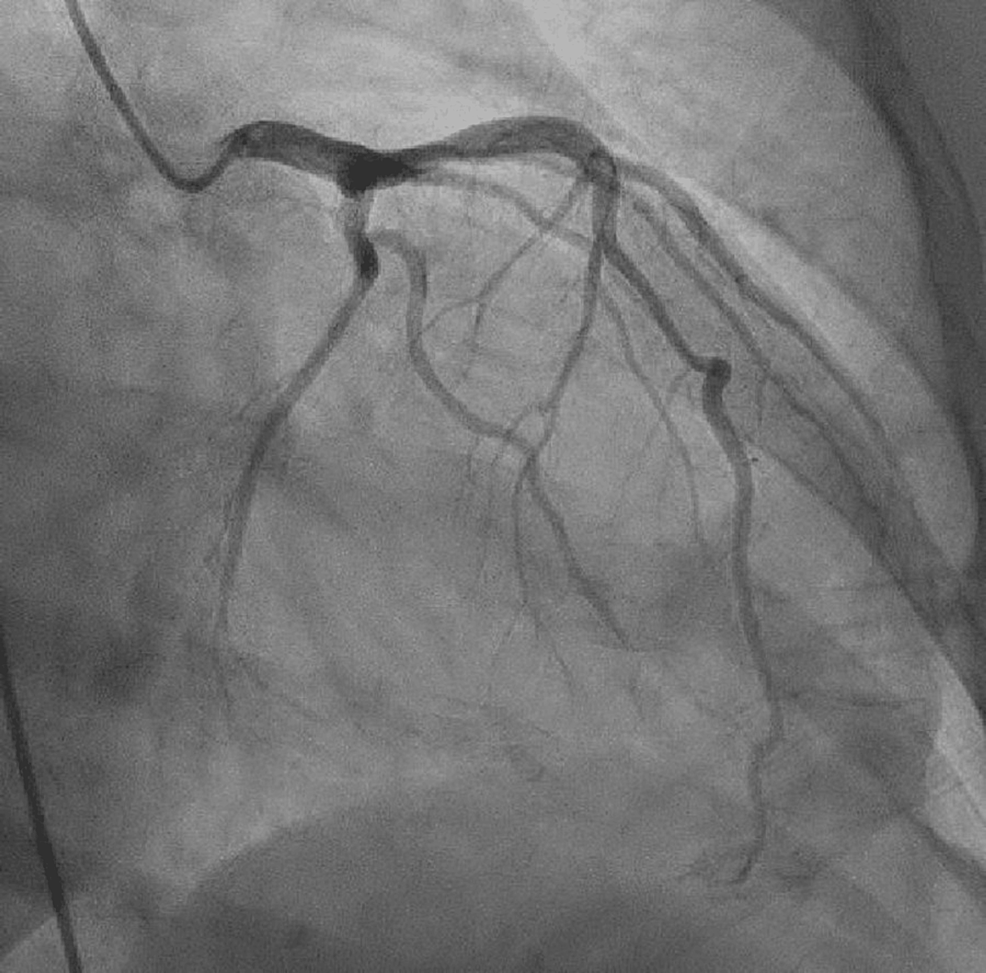

Cardiac catheterization performed on 28 October 2022, which showed

Cardiac catheterization performed on 28 October 2022, which showed Cardiac Catheterization Ejection Fraction A normal heart’s ejection fraction is between 55 and 70 percent. Ejection fraction is measured as a percentage of the total amount of blood in your heart that is pumped out with each heartbeat. 10k+ visitors in the past month When the heart squeezes, it's. A normal ejection fraction is 50 percent or. Ejection fraction is the fraction of the. Cardiac Catheterization Ejection Fraction.